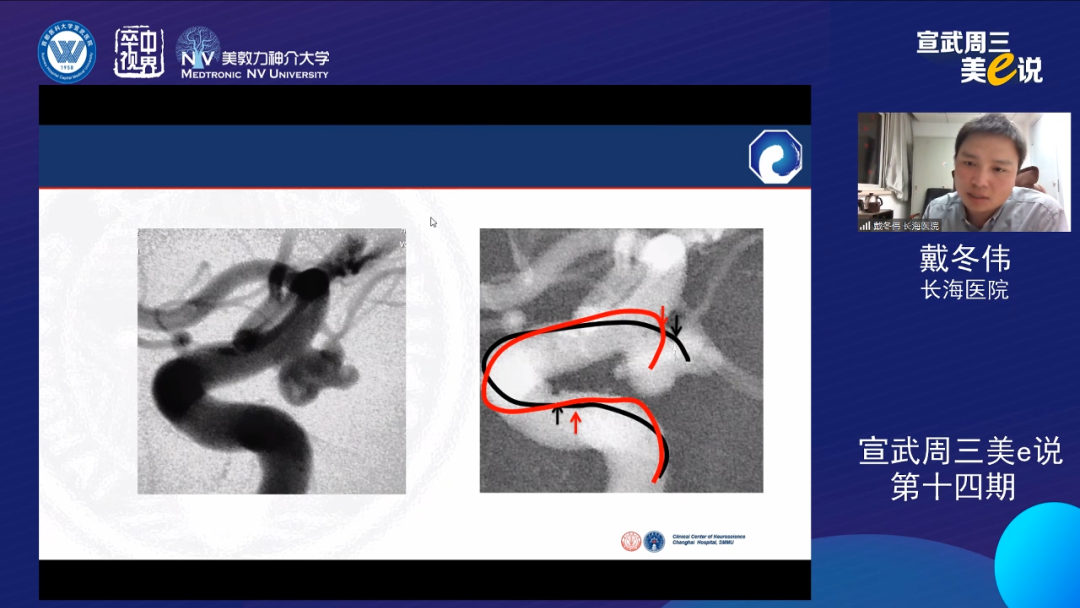

戴冬伟

上海长海医院

戴冬伟教授通过多个病例介绍了双微导管技术在各种复杂动脉瘤中的应用,体现了双微导管技术对于保护分支血管,避免支架抗聚,以及栓塞多子囊不规则动脉瘤的独特优势。同时戴教授也谈到了双微导管技术的局限性,包括瘤颈致密栓塞可能不足,可能导致弹簧圈部分突入载流动脉等。相对支架而言,双微导管技术可能需要更高的操作技巧。